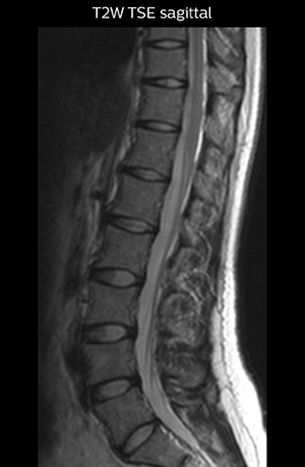

The key concept in MR neurography, Dr. Yabuki stresses, is the ability to directly visualize spinal nerves, versus inferring the presence of pathology indirectly. “Before NerveVIEW, we estimated compression of the nerve by looking for the presence or absence of fat signal on other MR images,” he says.

“For example, in sagittal images, when the presence of fat is observed in the intervertebral foramen, it suggests that there is a margin around the nerve. Similarly, the absence of fat indicates that the nerve is being compressed. So, we used to deduce nerve compression indirectly. With NerveVIEW, however, we can observe the condition of the nerves directly, regardless of the presence or absence of fat. We always prefer such direct observation of anatomy over having to make an inference about it.”

T2W sagittal and axial